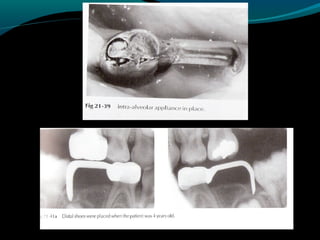

DISTAL SHOE

(Intra-alveolar,Eruption guidance

appliance)

o Used to maintain the space of a primary

second molar that has been lost before

the eruption of the permanent first

molar.

o An unerupted permanent first molar

drifts mesially within the alveolar bone if

the primary second molar is lost

prematurely.The result of the mesial

drifts is loss of arch length & possible

impaction of the second premolar.

DISTAL SHOE (Intra-alveolar,Eruption guidance appliance) oUsed to maintain the space of a primary second molar that has been lost before the eruption of the permanent first molar. o An unerupted permanent first molar drifts mesially within the alveolar bone if the primary second molar is lost prematurely.The result of the mesial drifts is loss of arch length & possible impaction of the second premolar.

• 54.